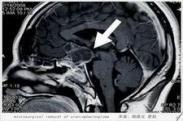

黏多糖病(muco polysaccharidosis,MPS)又稱Brailsford綜合征、Brailsford-Morquio綜合征、硫酸角質尿癥、離心性軟骨發育不良、畸形性軟骨-骨營養不良等。是一組先天性遺傳病,因黏多糖降解酶缺乏使酸性黏多糖不能完全降解,導致黏多糖積聚在機體不同組織,造成骨骼畸形、智能障礙等一系列臨床癥狀和體征。

- 常見癥狀:鞍鼻、短頸、肝脾腫大、脊柱彎曲、角膜混濁、四肢無力、桶狀胸、足外翻